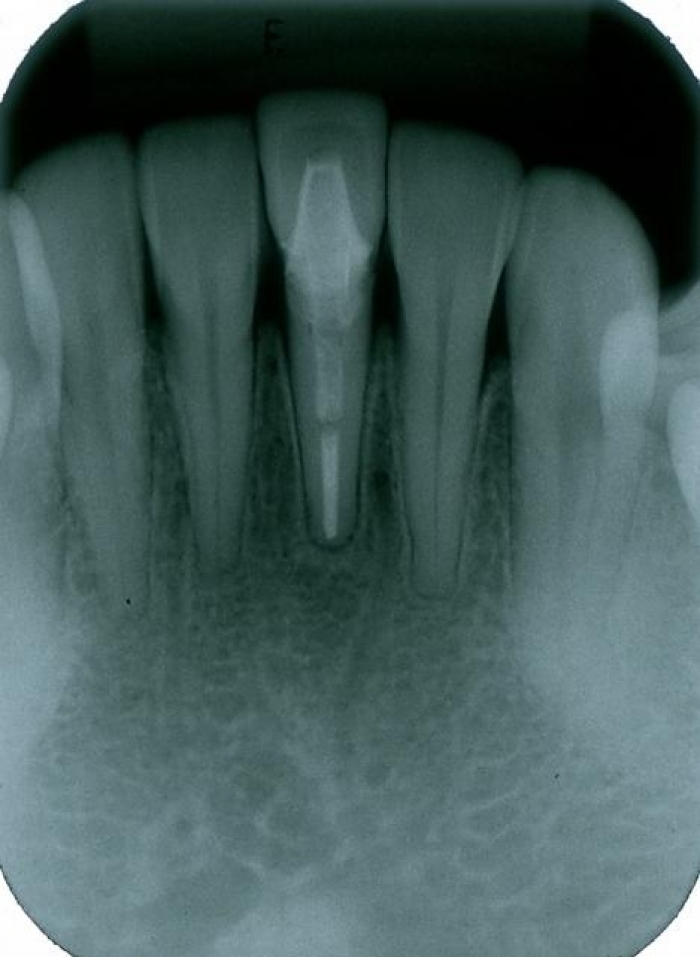

Imagem inicial

Imagem inicial do incisivo central inferior esquerdo fraturado

Raio x inicial